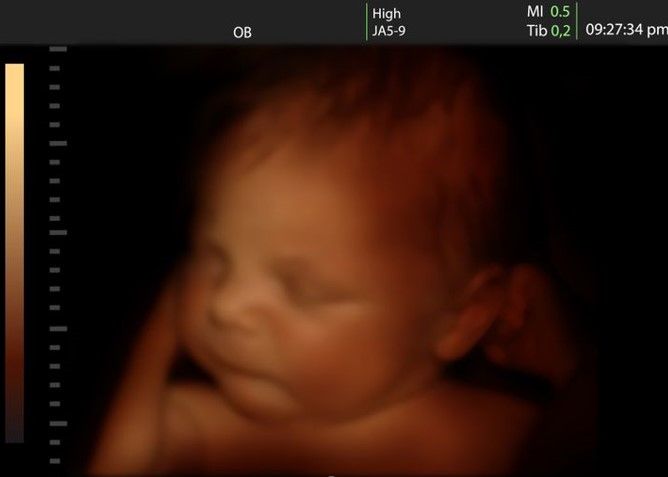

Dunyoda yoshligida bolali bo‘lishga intilmasdan, farzand ko‘rishni keyinroqqa surib qo‘yayotgan ayollar soni ko‘payib bormoqda. Turli mamlakatlar olimlari kech tug‘iladigan bolalarning aql-zakovati ota-onasining yoshi va boshqa omillar bilan bog‘liqligini aniqlab bergan keng ko‘lamli tadqiqotlar o‘tkazdi.

Bolaning aql-zakovati ota-onaning yoshiga bog‘liq

Har bir yangi tug‘ilgan chaqaloqda ota-onasida bo‘lmagan 70 ga yaqin mutatsiya mavjud. Bundan tashqari, ularning katta ulushi onadan emas, ota tomonidan o‘tadi: erkak qanchalik katta bo‘lsa, u bevosita zurriyodining kognitiv qobiliyatlarga ta’sir qiluvchi ko‘p sonli mutatsiyalarni beradi. Mutatsiyalar qanchalik ko‘p bo‘lsa, farzandning intellektual rivojlanishga moyilligi pastroq bo‘ladi. Boshqacha aytganda, otasining yoshi qanchalik katta bo‘lsa, farzand uchun unchalik yaxshi emas ekan.

Ona yoshi bilan bo‘lgan vaziyat biroz boshqacha. Ayol qanchalik katta bo‘lsa, bolaning intellektual rivojlanishi shunchalik yuqori bo‘ladi. Tadqiqotchilar bu yerda asosiy rolni genlar emas, balki ijtimoiy-madaniy omil o‘ynashini tan olishadi: katta yoshli ayol ma’lumotli, tajribali, u o‘zini yaxshi nazorat qila oladi va tavakkaliklarga moyil emas.

Qanday bo‘lmasin, statistik ma’lumotlar juda yosh onalarning farzandlari sekinroq rivojlanishini aniqlab berdi.